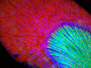

In the intricate microcosm of our bodies, different diseases may interact with each other. For example, researchers are exploring links between serous ovarian cancer (SEOC), the most common form of ovarian tumour, and the herpes simplex virus. Herpes infects over 65% of the world’s population, so is likely to occur in most SEOC patients. It also encodes small molecules, microRNAs, which manipulate gene activity; these are found in the ovaries of SEOC patients at higher levels than in healthy individuals. Each column here shows a section of cancerous tissue, with cell nuclei in blue, the tumour in yellow and surrounding connective tissues in green. In the last two columns, the merged images in the top row reveal the presence of microRNAs (in pink) in the tumour. Specific types of microRNAs are associated with more or less severe cancers, suggesting that further research into their function could help develop potential treatments.